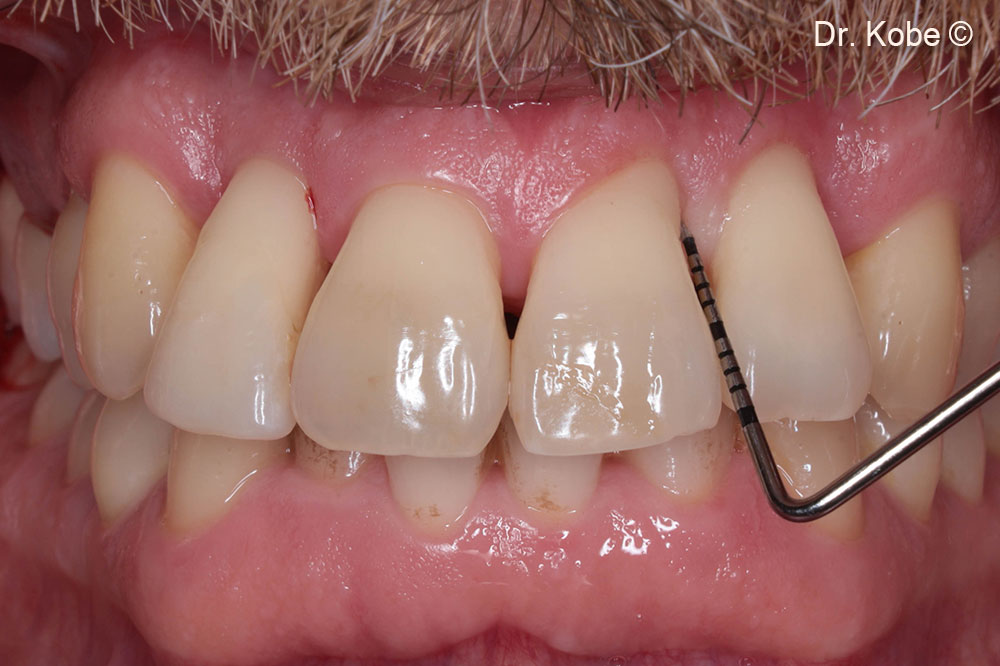

1-year follow-up in the first quadrant

1-year follow-up in the second quadrant